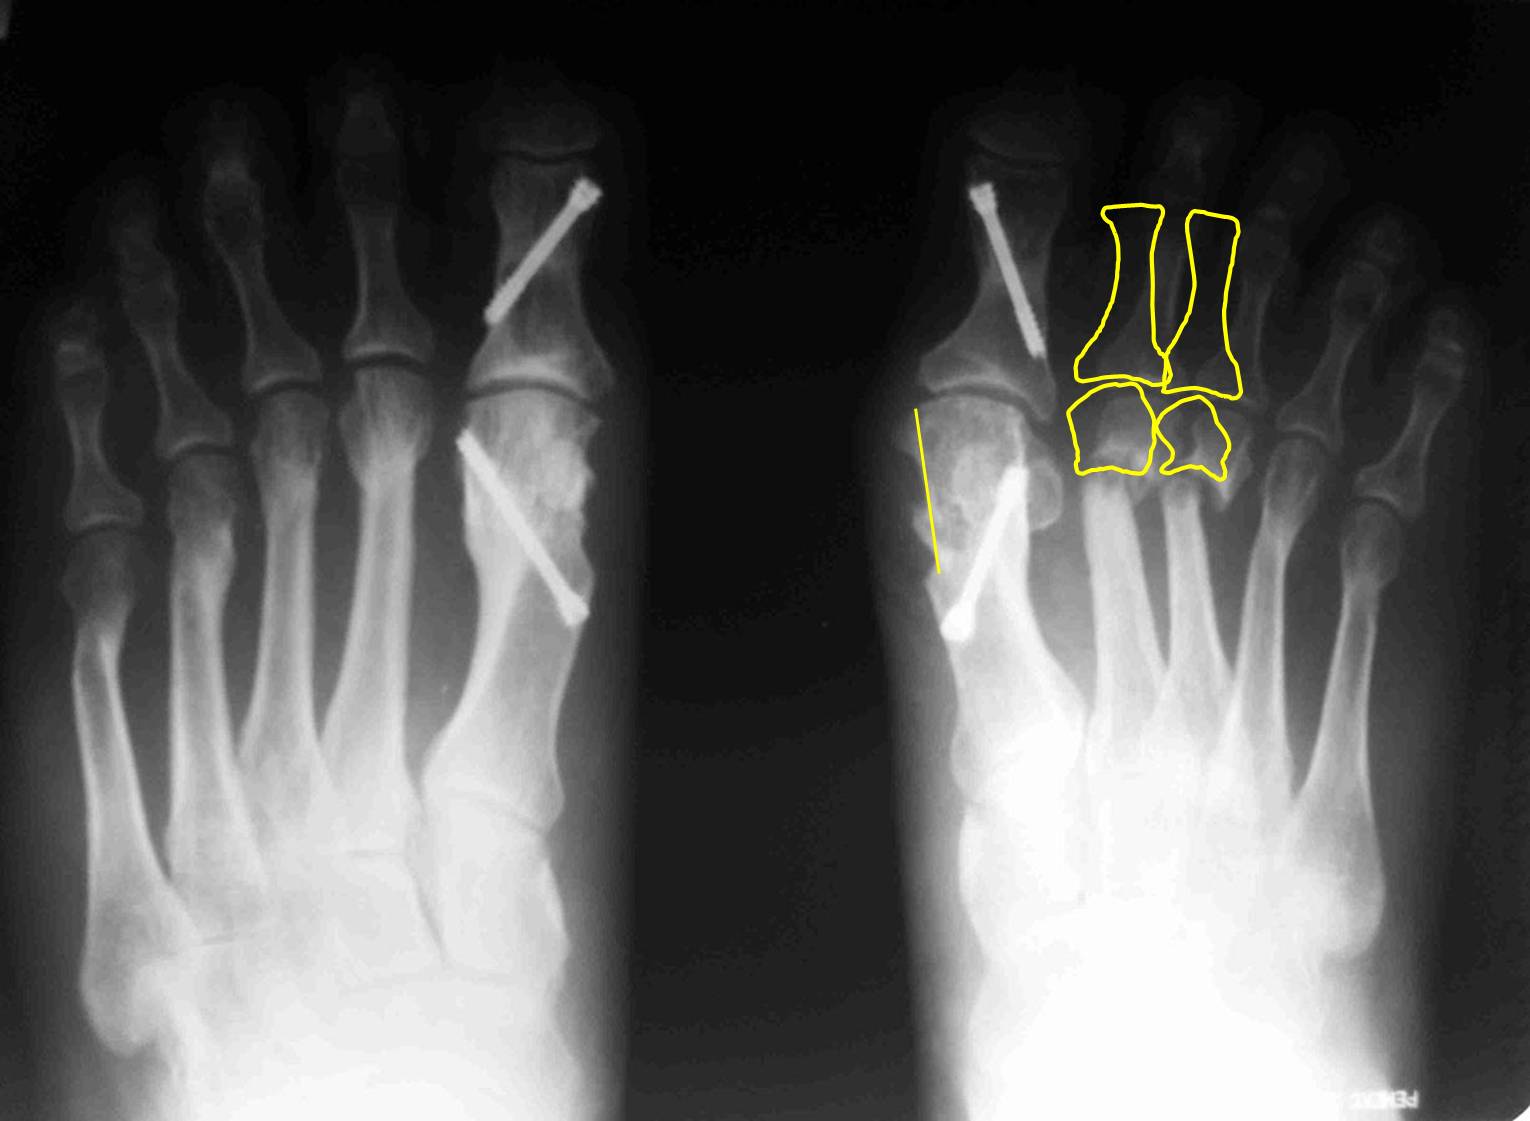

Уважаемые коллеги, я понимаю, что уже утомил вас оперированными стопами, но помогите еще с одним случаем Женщина около 50, активная, оперирована 1 год назад. Тип остеотомии в выписке не указан (похоже с 1-го по 5-ую + фаланги). Сожалею. что фото стопы не удалось выложить, клинически - выраженная девиация всех пальцев стопы слева. Что предпринять? Латеральный релиз, утягивание (лучшего синонима не нашел) медиальной капсулы+остеотомии 4-5 с нормальной повязкой? 1-ый луч - SERI (для жесткости остальных- к нему притянуть), но, головка и так скомпроментирована (или это не брать в расчет?)+ освежение ложняков+ коррегирующая остеотомия 4-5 Weil с фиксацией винтом (или без фиксации?). С фалангами что делать? Кажется, что ничего?

А чего Вы притесняетесь? Насчет "утомил вас оперированными стопами". Такая же ортопедия, как и вся остальная, обсуждаемая на форуме. Да еще сложный ревизионный случай. Изначально то все здорово было. Так бывает, к сожалению, когда все вроде правильно сделано, а в результате не складывается. Почему-то 2 из 10 плюсневых не срослись. На прошлогодней конференции AOFAS был доклад о неудачах после операций на стопе, в котором авторы выделили группу «нестрастальщиков»: пациентов, которые не срастаются без очевидных причин для этого. Может и здесь подобный случай. Из предложенного Вами плана не ясно, зачем делать SERI? Ее ведь сделали год назад. Только не стандартный вариант с фиксацией спицей, а более сложный, с внутренней фиксацией. Возможно, в этом была причина избыточной латерализации головок: подошвенные пластинки 1 и 2 плюснефаланговых суставов тесно связаны. Слишком радикальное уменьшение первого межплюсневого угла за счет латерального смещения головки первой плюсневой привело к дестабилизации нефиксированных остеотомий 2 и 3 плюсневых. И если сейчас еще больше переместить головку первой плюсневой кнаружи, это только усугубит ситуацию. На схеме я показал, в каком положении окажутся 2 и 3 пальцы в случае репозиции головок их плюсневых: расстояния между 1 и 2 лучами итак практически не остается. Я бы в данном случае подровнял внутренний контур головки 1 плюсневой, удалил винт из основной фаланги, выполнил латеральный релиз 1 плюснефалангового, эйкиноподобную остеотомию основной фаланги 1 пальца; репозицию головок 2-3 плюсневых с фиксацией их головок спицами на 4-6 недель и положив в область ложных суставов костную аутостружку или какой-нибудь искусственный заменитель кости. Если при этом пальцы не станут ровнее – выполнил бы остеотомии основных фаланг соответствующих пальцев. Без вмешательства на 4-5 плюсневых.